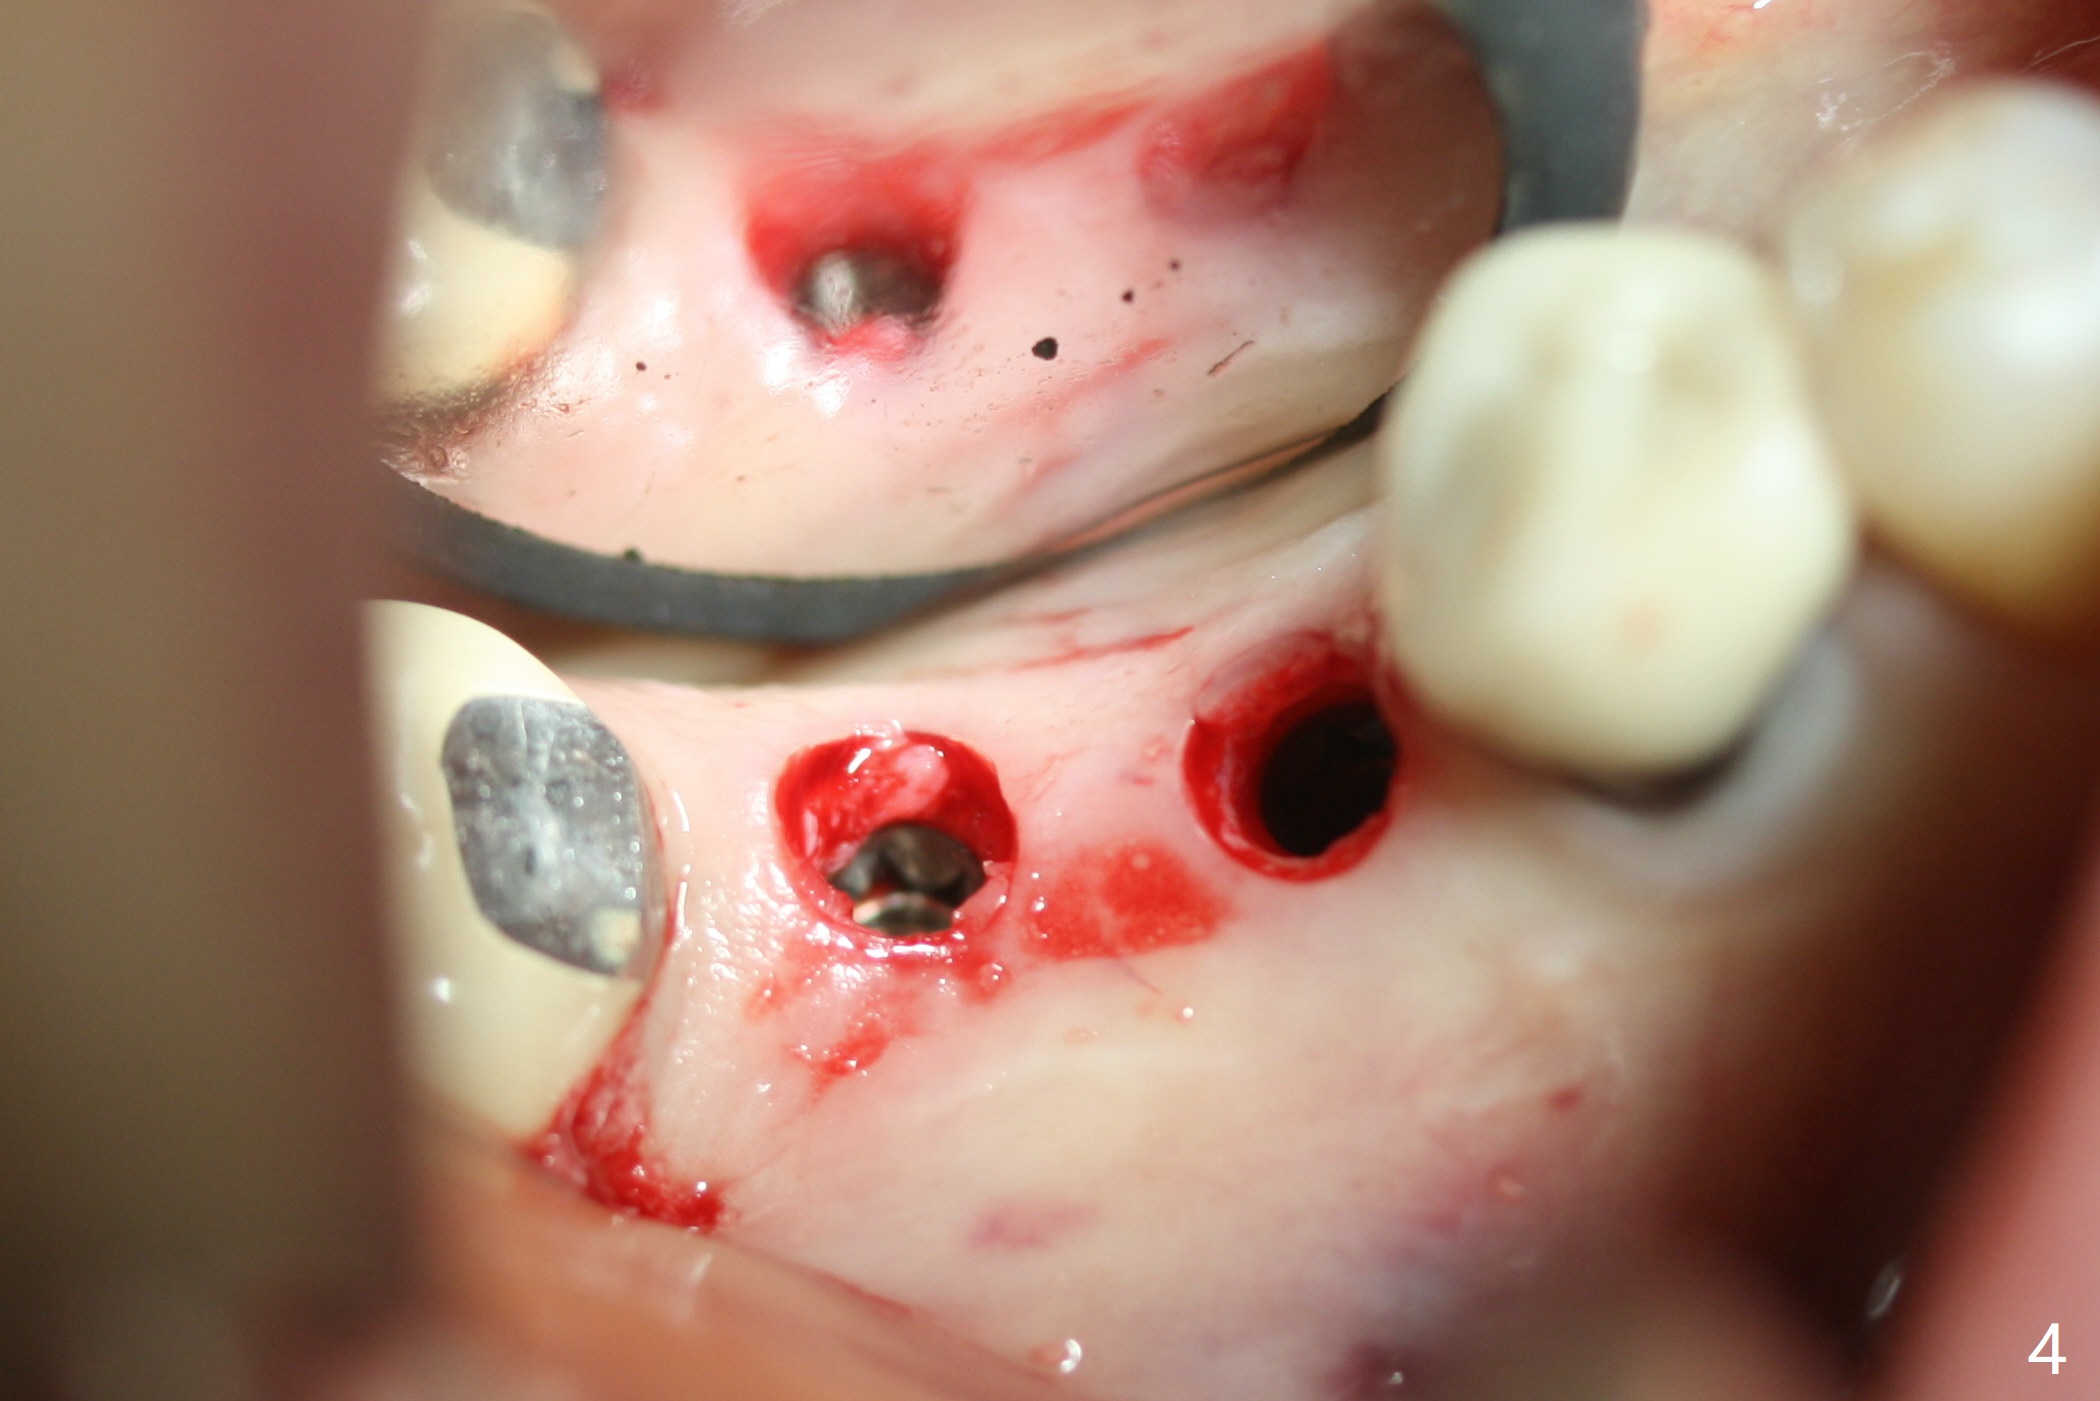

To reduce patient's expense, two implants are to be placed in narrow mesiodistal space (#30 and 31) free hand. Time is spent to determine where to place 4 mm tissue punch. When initial osteotomy is established (Fig.1), effort is paid to deciding whether the osteotomy is close to the Inferior Alveolar Canal (Fig.2 red dashed line). Since the gingiva is thin (Fig.4), implants switch to bone level ones (Fig.3,4). To have enough space between implants and the neighboring tooth, two of 3.5 mm implants are placed. Because of the limited vertical restoration height, the implants are chosen intraoperatively to be short and placed deep (Fig.3). Guided surgery planning can solve these pieces of dilemma beforehand.